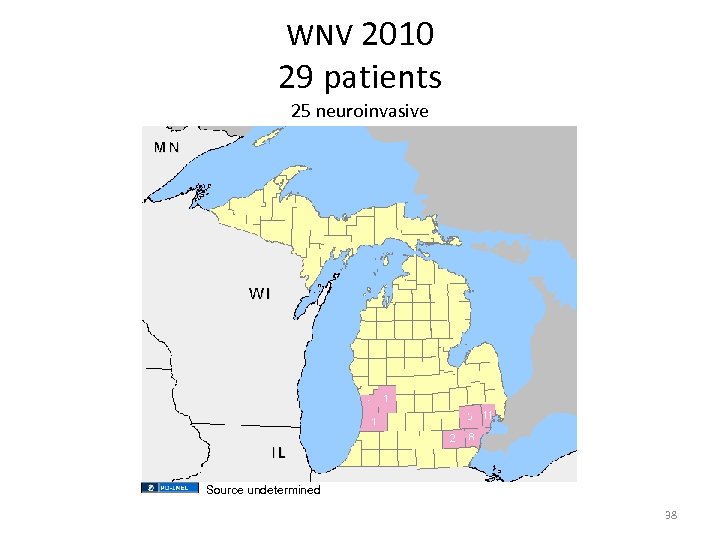

WNV 2010 29 patients 25 neuroinvasive Source undetermined 38